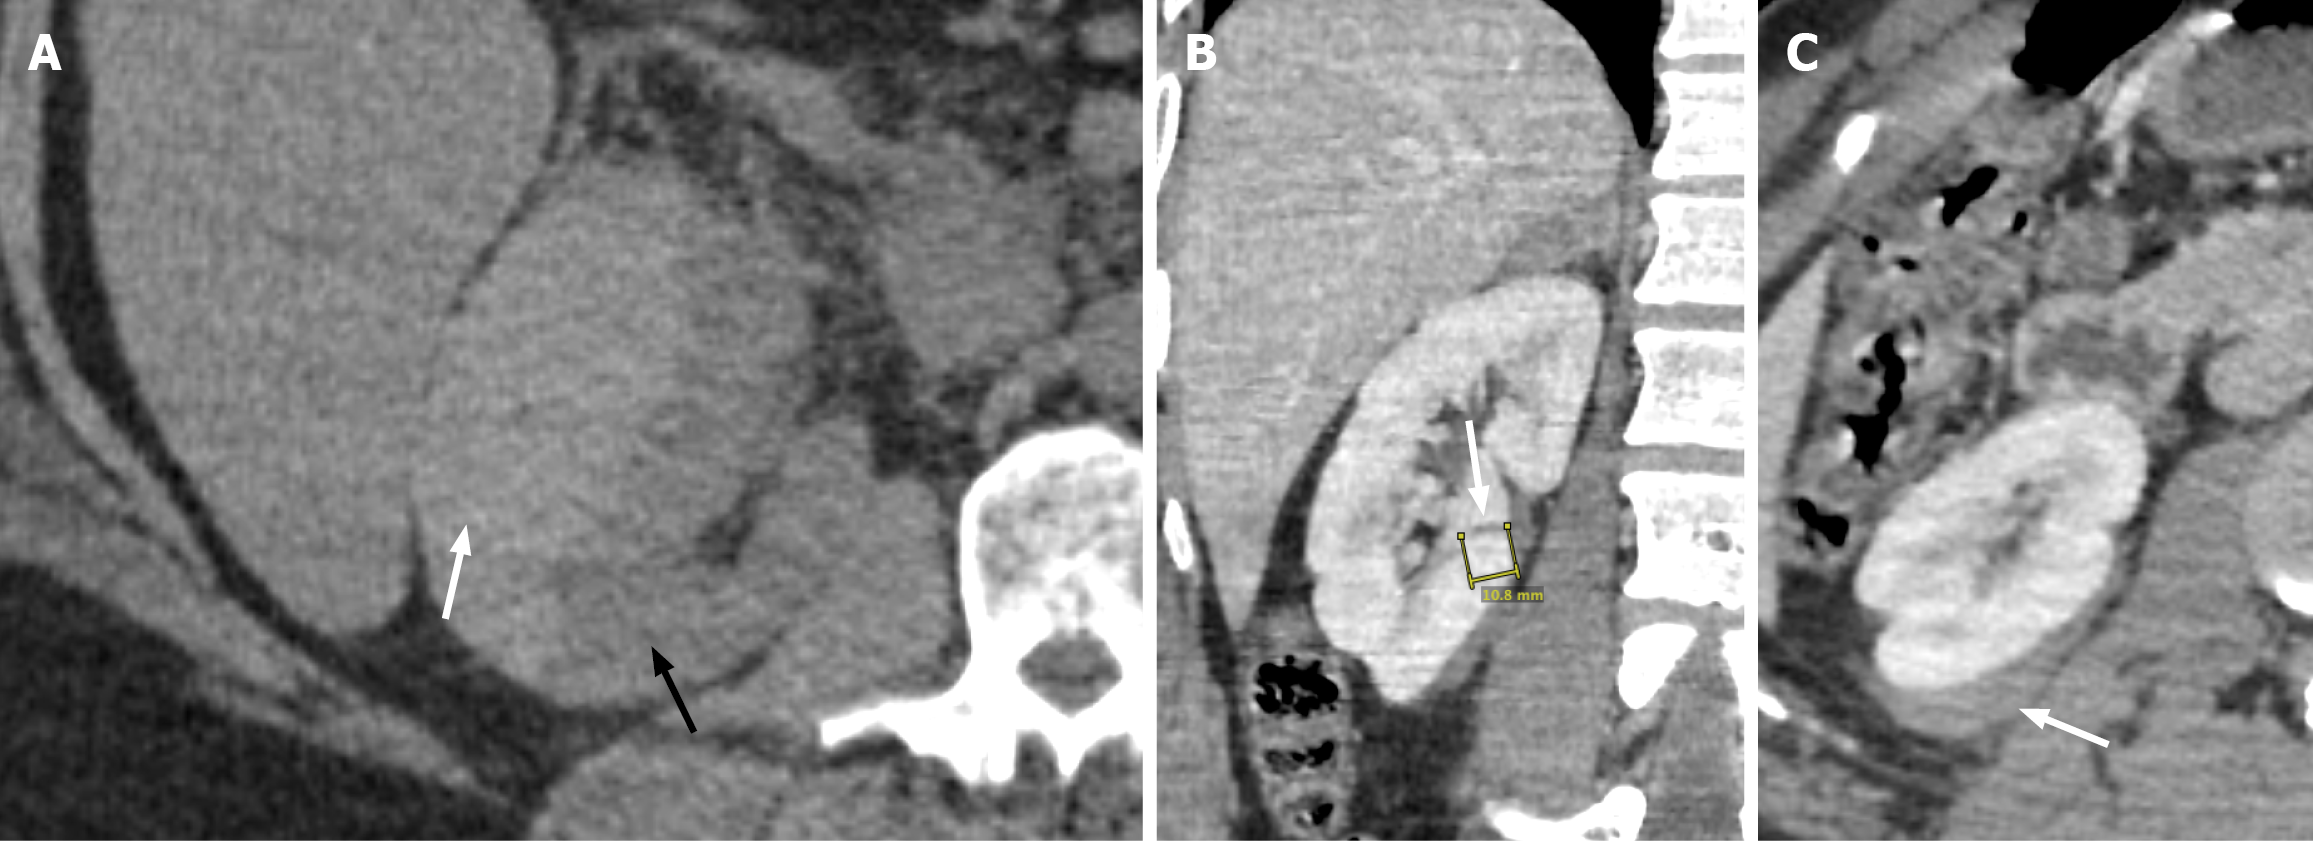

Figure 1 Grade I and II renal Injury.

A: Axial view of the non-contrast enhanced computed tomography of the right kidney demonstrates a lentiform-shaped hyperattenuating subcapsular collection (white arrow) with mass effect on the adjacent renal parenchyma (black arrow), compatible with renal subcapsular hematoma and grade I renal injury; B: Coronal view contrast-enhanced computed tomography of the right kidney demonstrates a linear hypoattenuation (white arrow) measuring > 1 cm in length, consistent with renal laceration; C: The axial view shows a slightly iso- to hyperdense perirenal collection (white arrow), consistent with a perirenal hematoma. The constellation of findings is compatible with grade II renal injury.